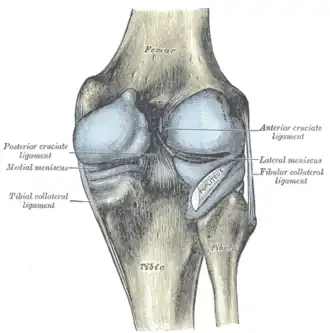

Ligaments

The ligaments surrounding the knee joint offer stability by limiting movements and, together with the menisci and several bursae, protect the articular capsule.[19]

Intracapsular

The knee is stabilized by a pair of cruciate ligaments. These ligaments are both extrasynovial, intracapsular ligaments.[20] The anterior cruciate ligament (ACL) stretches from the lateral condyle of femur to the anterior intercondylar area.[13] The ACL prevents the tibia from being pushed too far anterior relative to the femur.[13] It is often torn during twisting or bending of the knee.[21] The posterior cruciate ligament (PCL) stretches from medial condyle of femur to the posterior intercondylar area. This ligament prevents posterior displacement of the tibia relative to the femur.[13] Injury to this ligament is uncommon but can occur as a direct result of forced trauma to the ligament.

The transverse ligament stretches from the lateral meniscus to the medial meniscus. It passes in front of the menisci. It is divided into several strips in 10% of cases.[10]: 208 The two menisci are attached to each other anteriorly by the ligament.[22] The posterior (of Wrisberg) and anterior meniscofemoral ligaments (of Humphrey) stretch from the posterior horn of the lateral meniscus to the medial femoral condyle. They pass anterior and posterior to the posterior cruciate ligament respectively.[13][10]: 208 The meniscotibial ligaments (or "coronary") stretches from inferior edges of the menisci to the periphery of the tibial plateaus.

Extracapsular

The patellar ligament connects the patella to the tuberosity of the tibia. It is also occasionally called the patellar tendon because there is no definite separation between the quadriceps tendon (which surrounds the patella) and the area connecting the patella to the tibia.[23] This very strong ligament helps give the patella its mechanical leverage[24] and also functions as a cap for the condyles of the femur. Laterally and medially to the patellar ligament, the lateral and medial retinacula connect fibers from the vasti lateralis and medialis muscles to the tibia. Some fibers from the iliotibial tract radiate into the lateral retinaculum and the medial retinaculum receives some transverse fibers arising on the medial femoral epicondyle.[10]: 206

The medial collateral ligament (MCL a.k.a. "tibial") stretches from the medial epicondyle of the femur to the medial tibial condyle. It is composed of three groups of fibers, one stretching between the two bones, and two fused with the medial meniscus. The MCL is partly covered by the pes anserinus and the tendon of the semimembranosus passes under it.[10]: 206 It protects the medial side of the knee from being bent open by a stress applied to the lateral side of the knee (a valgus force).[10]: 206

The lateral collateral ligament (LCL a.k.a. "fibular") stretches from the lateral epicondyle of the femur to the head of fibula. It is separate from both the joint capsule and the lateral meniscus.[10]: 206 It protects the lateral side from an inside bending force (a varus force). The anterolateral ligament (ALL) is situated in front of the LCL.

Lastly, there are two ligaments on the dorsal side of the knee. The oblique popliteal ligament is a radiation of the tendon of the semimembranosus on the medial side, from where it is direct laterally and proximally. The arcuate popliteal ligament originates on the apex of the head of the fibula to stretch proximally, crosses the tendon of the popliteus muscle, and passes into the capsule.[10]: 206

Cruciate ligaments -

Left knee-joint from behind, showing interior ligaments. -